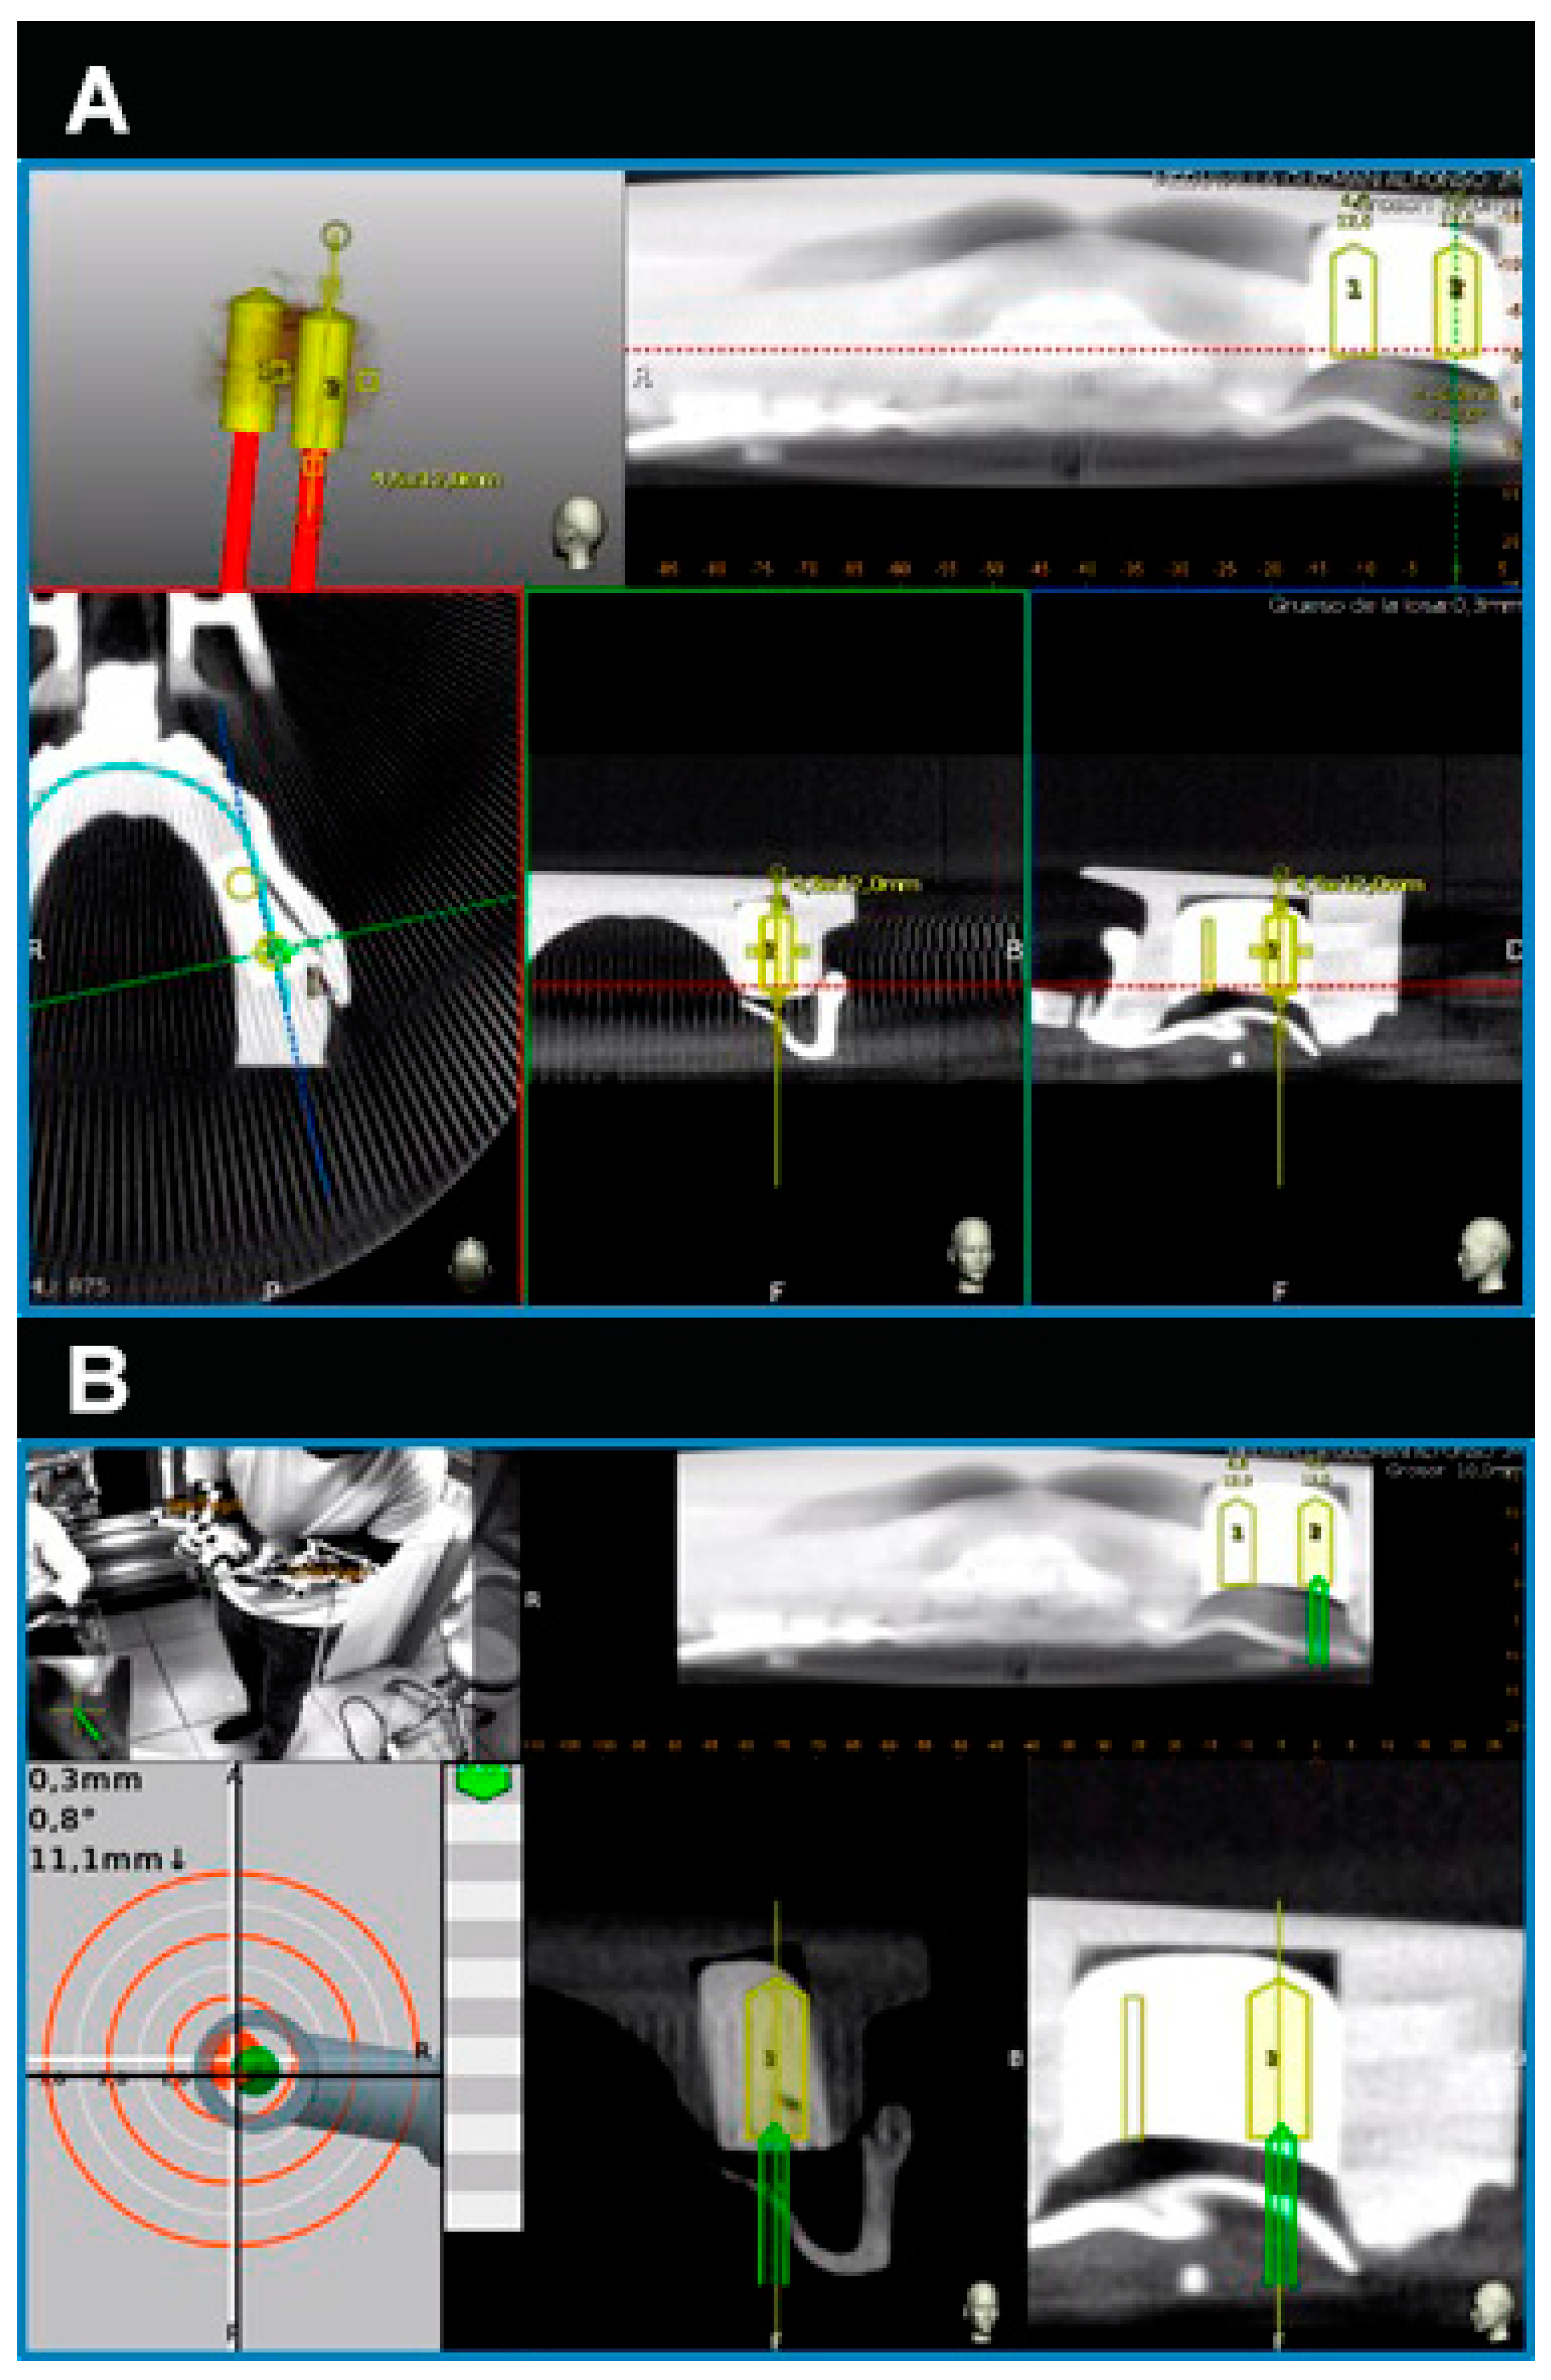

Calibration In Dynamic Navigation Surgery In Implamt

Browse our specialized Calibration In Dynamic Navigation Surgery In Implamt portfolio with numerous expertly curated photographs. optimized for both digital and print applications across multiple platforms. providing reliable visual resources for business and academic use. Each Calibration In Dynamic Navigation Surgery In Implamt image is carefully selected for superior visual impact and professional quality. Perfect for marketing materials, corporate presentations, advertising campaigns, and professional publications All Calibration In Dynamic Navigation Surgery In Implamt images are available in high resolution with professional-grade quality, optimized for both digital and print applications, and include comprehensive metadata for easy organization and usage. Our Calibration In Dynamic Navigation Surgery In Implamt collection provides reliable visual resources for business presentations and marketing materials. Whether for commercial projects or personal use, our Calibration In Dynamic Navigation Surgery In Implamt collection delivers consistent excellence. The Calibration In Dynamic Navigation Surgery In Implamt archive serves professionals, educators, and creatives across diverse industries. Regular updates keep the Calibration In Dynamic Navigation Surgery In Implamt collection current with contemporary trends and styles. Advanced search capabilities make finding the perfect Calibration In Dynamic Navigation Surgery In Implamt image effortless and efficient. Multiple resolution options ensure optimal performance across different platforms and applications.